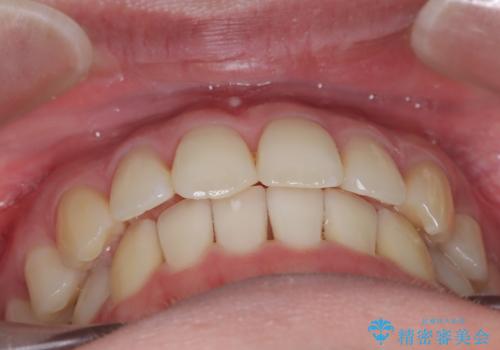

【インビザライン】 前歯の反対咬合を治したい

左下5番は先天性欠損のため乳歯は抜歯しインプラントにて欠損補綴しています。